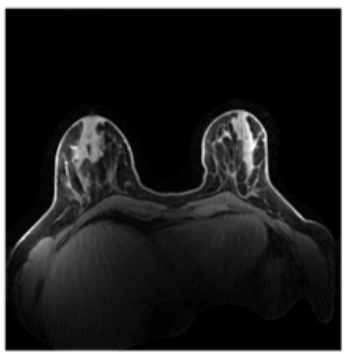

Segmentation-guided reconstruction pipeline for accelerated breast DCE MRI with robust temporal fidelity and reduced undersampling artifacts.

The project integrates tissue-prior segmentation with ELITE reconstruction to improve image quality in highly accelerated dynamic MRI scans.